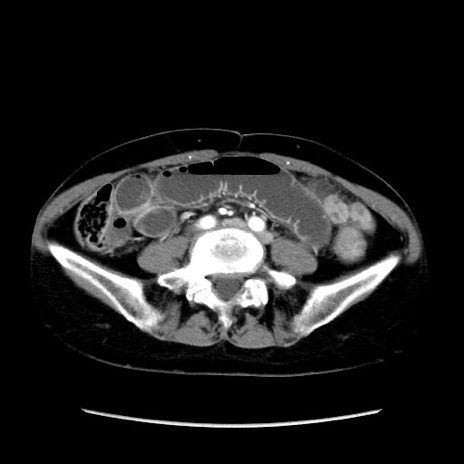

症例32(横断像)

【症例】40歳代 女性

【主訴】上腹部痛、嘔気・嘔吐

【現病歴】約9時間前頃から急に上腹部痛、嘔気、嘔吐が出現。改善しないため救急要請。

【既往歴】子宮頚癌(広汎子宮全摘術、放射線療法)、腸閉塞

【身体所見】腹部:平坦、軟、腸雑音亢進、上腹部を中心に腹部全体に圧痛あり。

【データ】WBC 8400、CRP 0.03